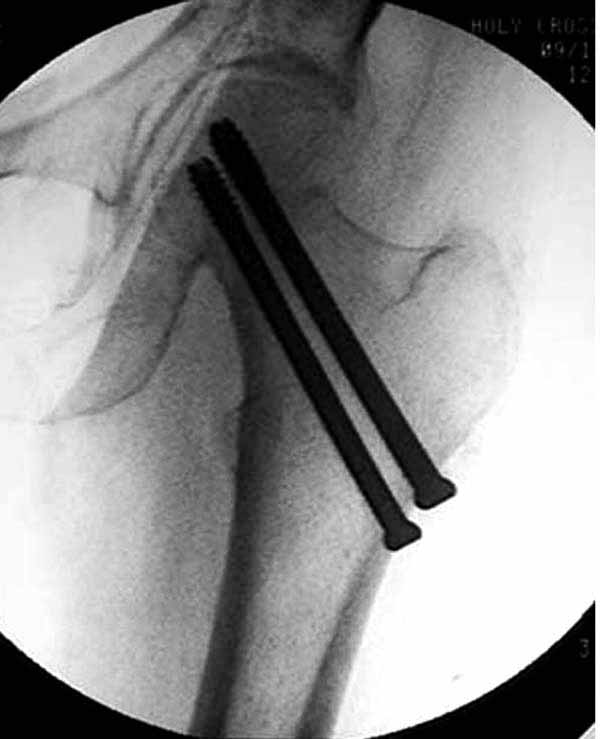

Пациентка Ш. 76 лет, 11 дней назад прооперирована по поводу вколоченного субкапитального перелома шейки левой бедренной кости, 3-мя канюлированными винтами. Вчера пациентка упала в палате. И вот результат- подимплантатный подвертельный перелом левой бедренной кости. Уважаемые коллеги, пожалуйста посоветуйте какой метод дальнейшего лечения предпринять дальше.Соматически пациента повышенного питания, страдает варикозной болезнью нижних конечностей.Из предложенных вариантов коллег - целллокастовая укороченная кокситная повязка, скелетное вытяжение сроком на 40-45 суток - отпали сразу, так как необходимо активизация пациентки.На данный момент рассматриваем следующие варианта реостеосинтеза:(наличие технических возможностей) 1. Длинная Gamma 3 Stryker (с предварительной интраоперационной фиксацией головки спицами).2. Трохантерный штифт DePuy с 2-мя метафизарными винтами в проксимальном отделе, (также с интраоперационной фиксацией головки спицами. Очень настораживает стабильность фиксации с проксимальном отделе с связи с выборкой костной ткани ранее находящимися там канюлированными винтами. Сейчас пациентка находится на скелетном вытяжении, с дисциплинирующим грузом. Операция планируется после праздников. Заранее извиняемся за качество и неполное соответствие проекций на R-ммах (R-служба отдельная песня). При интраоперационном ЭОП-контроле винты в аксиальной проекции разнесены по шейке.

Как отметили коллеги, необходимо обратить внимание на последовательность введения каннюлированных шурупов. Рекомендуется введение в форме “V”, т.е основанием вниз, потому что в другой последовательности за счет увеличения стресса латерального кортекса имеется риск перелома. За редким исключением удается установить Guide wire с первой попытки и многоразовые пробы спицей увеличивают стресс. Небольшая травма может привести к перелому.

Работа Burstein AH and Wright TM: Fundamentals of Orthopaedic Biomechanics. Williams & Wilkins, Baltimore, pp. 160-169, 1994 доказывает, что шурупы, введенные на уровне малого вертела или ниже, приводят к осложнению. Введенные шурупы под 135 и больше градусов в 20% осложнились подвертельными переломами бедра.